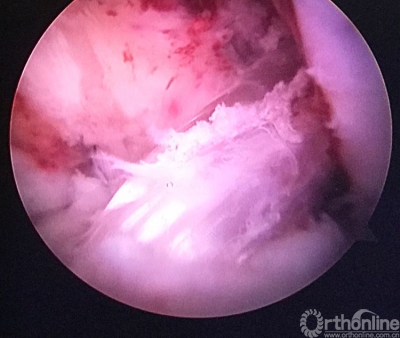

关节镜检查见重建的韧带已经消失。

原来重建的ACL胫骨隧道内口偏前(等离子刀头所指处)。

现等离子刀头所指处应该为正确的内口定位,原内口与此处相距较远。

现等离子刀头所指处为外侧半月板前角游离缘。左下方2个等离子刀烧灼处为原内口及准备返修的内口。